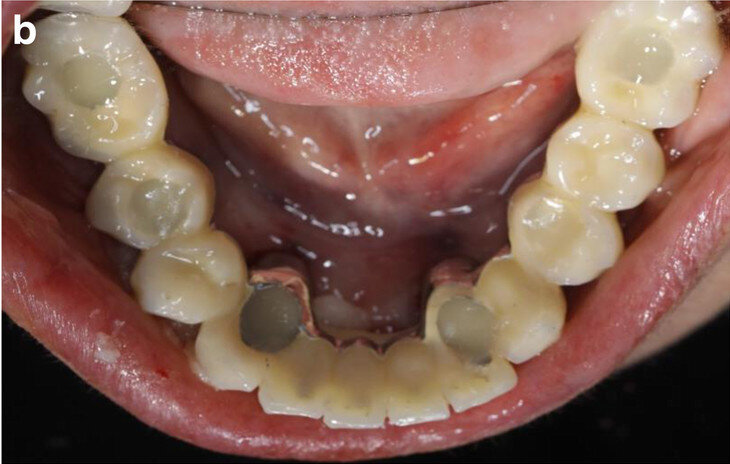

Figs. 2a & b: Initial dental status: right side (a) and left side (b).

The dental status showed acceptable oral hygiene and some teeth with Grade III mobility (teeth #41, 31, 32, 18 and 28) and local periodontal problems, including horizontal bone loss (teeth #42, 41, 31, 32, 33, 18, 17, 27 and 28). Teeth #42 and 33 were healthy and not mobile. The alveolar crest in the lateral mandible area showed clinically a wide shape with thick keratinised mucosa. The initial panoramic radiograph revealed stable crestal bone in the lateral mandibular area (Figs. 1–3). Thus, in the lower jaw, the single-tooth prognosis was fair for teeth #47, 42 and 33, and hopeless for teeth #41, 31 and 32.[24]